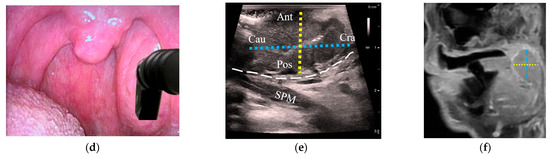

Tumor size was estimated with both US and MRI in 18/21 patients with OPCs (86%); three patients whose tumors could not be delineated on US were excluded from analysis. In all cases, outpatient US was performed a median of 5 days after MRI (interquartile range: −2 to 10 days). A high correlation between US and MRI was observed when comparing the tumor diameter along the US depth axis, which corresponded to the anteroposterior diameter (R = 0.80, Figure 3a). The lateral US axes corresponding to craniocaudal (R = 0.54) and mediolateral diameters (R = 0.49) demonstrated moderate correlation with MRI (Figure 3b,c). Figure 4 illustrates transoral transducer orientations and the corresponding US axes compared to MRI.

Figure 4.

Comparison of tumor diameters between transoral US and corresponding MRI images of a stage-T2 palatine tonsil HPV+ SCC: (a) a patient with an asymmetric left palatine tonsil with an inserted hockey-stick ultrasound transducer placed onto the tonsil in a transverse plane; (b) transverse US reveals a palatine tonsil tumor. Tumor diameters are represented from medial (Med) to lateral (Lat) with a red dotted line and from anterior (Ant) to posterior (Pos) with a yellow dotted line; (c) axial MRI with the corresponding diameters as in (b, red and yellow dotted lines); (d) transducer oriented in the sagittal plane; (e) sagittal US with the cranial (Cra) to caudal (Cau) diameter added (blue dotted line) along with Ant-Pos (yellow dotted line); (f) sagittal MRI with the corresponding diameters as in (e, blue and yellow dotted lines). US: ultrasound; MRI: magnetic resonance imaging; HPV+ SCC: human papillomavirus-positive squamous cell carcinoma; ICA: internal carotid artery; ECA: external carotid artery; MPM: medial pterygoid muscle; SPM: stylopharyngeus muscle; white dashed line: constrictor muscle; Ant: anterior; Pos: posterior; Med: medial; Lat: lateral; Cra: cranial; Cau: caudal.